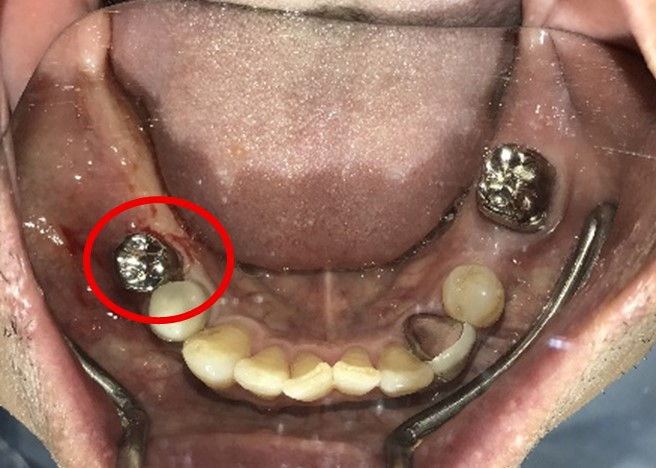

Before

※赤丸を抜歯しました。

After